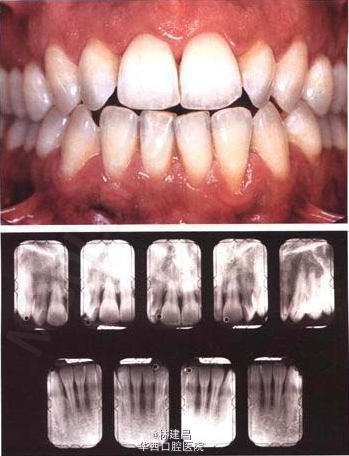

口内检查:全口口腔卫生欠佳,牙石(+),软垢(+),少量色素。牙龈中度红肿,BI=4,PD=2-9mm,前牙GR=0-4mm,松动度及

根分叉病变及余详见牙周大表。

曲断示:全口牙槽骨水平吸收根长1/2,36近中牙槽骨角形吸收。18,28,38,48阻生。

张大夫的这例侵袭性牙周炎的case不错,很典型的牙周组织破坏程度与菌斑刺激因素不一致。34岁的女性看牙周大表的情况确实挺严重,张大夫能谈下对侵袭性牙周炎的治疗中...查看全部

这个牙周检查记录表挺好的,牙周病的患者最好每次复诊都能记录,以便于对比,观察基础治疗及口腔维护的疗效。侵袭性牙周炎的话最好还是要辅助药物治疗